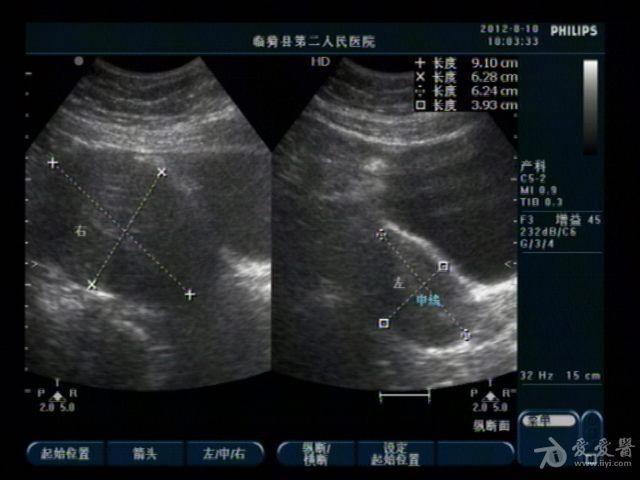

典型双子宫图像

前几天,我们科来了一位老病号,一年前剖腹产患者。当时手术证实“双子宫”今天超声图像可见一大一小两个子宫,右侧较大拟诊“子宫内膜异位症”。患者有经期腹痛史。

患者今年29岁,现生有一孩,就是剖宫产那个孩子。具体是那个子宫患者也不清楚,因在外地做的手术我们未能得到准确资料。患者近几个月来有明显的痛经史